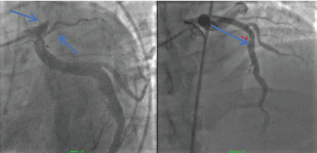

During angiography Type 1 CAE was identified. The right coronary artery (RCA), Circumflex coronary artery (Cf) and LAD were all large luminal vessels consistent with coronary artery ectasia. (Figure 3 and Figure 4) The patient had a symptomatic episode of ventricular tachycardia that was hemodynamically compromising and was managed with cardioversion. The patient recovered and was treated with ASA and ticagrelor for 18 months and then changed to just ASA. He remained active and free of cardiovascular symptoms.

Figure 3: Ectatic right coronary artery. View Figure 3

Figure 4: Ectatic circumflex coronary artery (Blue arrows). View Figure 4

The 2018 presentation was consistent with a NSTEMI. Coronary angiography revealed a patent RCA (Figure 9).

Figure 9: Ectatic RCA. View Figure 9

Thrombus was identified in an ectatic circumflex coronary artery (Figure 10).

Figure 10: Circumflex Thrombus: red outline 2018. View Figure 10

Thrombus was identified in the LAD (Figure 11).

Figure 11: LAD clot (blue arrow) 2018. View Figure 11